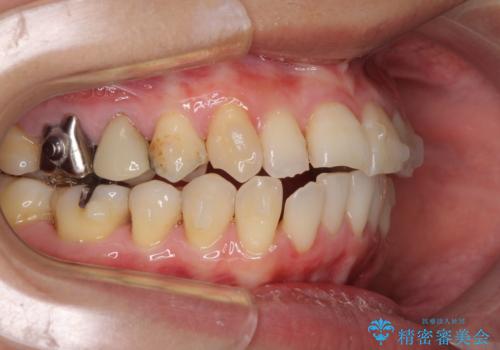

- 前歯のデコボコを気にして来院された患者様です。

上下前歯の先端同士が接触する切端咬合であったため、上顎は歯列を拡大し、下顎はIPR(歯と歯の間を削る)により叢生を解消しながら歯列を小さくすることとしました。

矯正装置にはインビザラインを用いることとしました。

治療途中に前歯に歯髄充血を思わせる痛みが認められたため、無理のない歯の移動と頻繁な経過観察を行いました。

切端咬合はスムーズに解消され、前歯の負担を軽減させることができました。